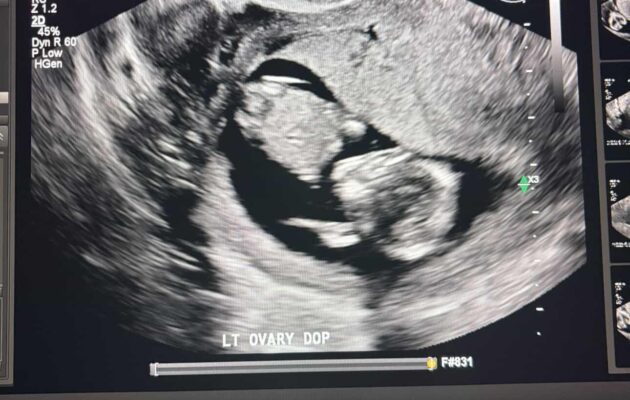

Week 20 out of 40 of Pregnancy!

I can’t believe we are halfway through this pregnancy! I have felt great throughout this whole experience, only dealing with a couple headaches. We heard baby’s heartbeat last week for the first time. Everything sounded healthy and normal. We have our anatomy scan on 10/5. I am excited and nervous for this scan. Excited to see baby again. Nervous to see if there are any issues. Either way, we are counting down the days till we meet our little nugget.